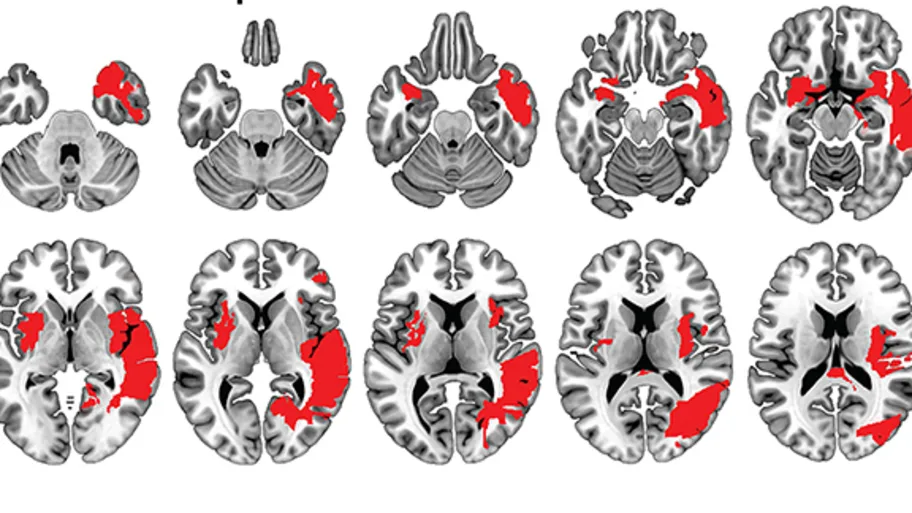

As well as confirming existing knowledge about the anti-aging effects of voluntary physical exercise – older mice that exercised retained the ability to change eye dominance in comparison to those that didn’t – the study also revealed some exciting new findings. Those mice that had free-access to a running wheel were able to maintain ocular dominance plasticity after suffering a stroke, compared to those that didn’t.

“We found that mice with free access to a running wheel throughout their life preserved a more juvenile brain into adulthood and were able to prevent the negative effects of a stroke,” reveals Kalogeraki.

That was not all – in addition, the researchers observed that exercise could even be used therapeutically after suffering a stroke. “We also found that mice with no previous access to a running wheel showed an equally positive recovery if voluntary exercise started after a stroke had occurred,” adds Dr. Justyna Pielecka-Fortuna, co-author of the study.